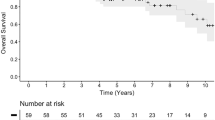

Twenty patients showed tumour progression during the follow-up period, the majority within 5 years from proton treatment (13/20). In 12 cases (60%) radiological progression of the tumour had been noticed even before treatment. The actuarial 5- and 10-year PFS rates that occurred after Kaplan Meier analysis were 93% and 85% (Fig. 2).

The 5- and 10-year PFS rate in the current study were 93% and 85% respectively which is satisfactory, especially with regard to the large tumour volumes (mean target volume 13 cm3), and comparable with the results from other studies [15, 26, 41, 42]. No deaths could be directly attributable to the radiation treatment. Complications were seen in 9.4% of the patients but the majority were either asymptomatic or treated pharmacologically with good effect (i.e. hypopituitarism).